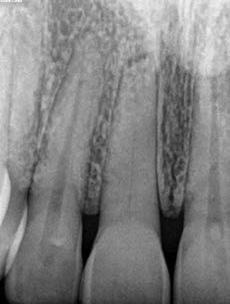

1. a–f ábrák: A cingulumon keresztül gömbfúróval kialakított hozzáférés a trepanációs kavitás labiális irányba történő túlzott mértékű kiterjesztését eredményezheti, és ez lényegesen növelheti a perforáció esélyét (a). A guttapercha átsejlik a lágyrészek alatt (b). Klinikailag igazolt perforáció (c). A preoperatív sagittális irányú CBCT-szeleten jól látható a labiális perforáció (d). Labiális irányú perforáció (fekete nyíl; e). A tényleges gyökércsatorna (piros nyíl; f).

2. a-b ábrák: A cingulumon keresztül gömbfúróval végzett trepanálás túlzott pericervikális dentin áldozattal, fordított tölcsér effektussal és perforációk kialakulásával járhat (fehér nyíl).